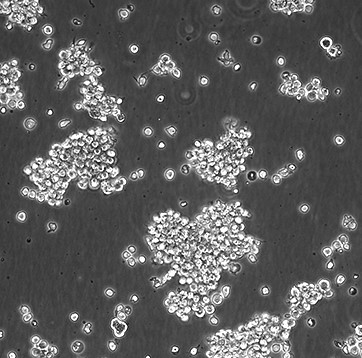

SU-DHL-2

SUDHL2; SUDHL-2; Su-DHL-2; SU-DHL2; SuDHL 2; Stanford University-Diffuse Histiocytic Lymphoma-2; DHL-2

RPMI 1640 + 10%澳洲胎牛血清

Temperature: 37°C ; Carbon dioxide (CO₂), 5%

悬浮细胞